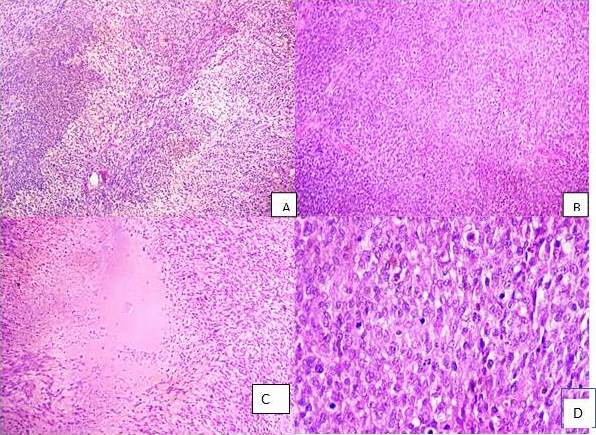

La pieza quirúrgica de la mastectomía total fue procesada en el laboratorio de la unidad de patología, observándose en el estudio macroscópico (Figura 5) hacia unión de cuadrantes externos y a 0,2 cm del borde de resección profundo (músculo), una lesión de aspecto tumoral de 16,5 cm x 6 cm x 5 cm, de bordes bien delimitados, pardo-amarillenta, con áreas de hemorragia, siendo el resto del tejido mamario de aspecto usual. El diagnóstico histopatológico fue: “sarcoma de alto grado (grado 2), según la clasificación de la Federación Francesa del Centro de Cáncer Grupo de Sarcomas”, con actividad mitótica de 20 mitosis en 10 campos de mayor aumento, presencia de necrosis en menos del 50 %, con áreas densamente celulares de células fusiformes alternas con otras menos celulares y presencia de células epitelioides (Figura 5). Los bordes de resección de la mastectomía estuvieron libres de lesión.

Se realizó estudio de inmunohistoquímica con polímero marcado con peroxidasa conjugada al anticuerpo secundario, realizándose inmunorreacciones para los siguientes anticuerpos: vimentina, citoqueratina AE1/AE3 (CKAE1/AE3), actina músculo liso (AML), desmina, CD34, proteína S100, enolasa, receptores de estrógenos (RE), receptores de progesterona (RP) y Ki67. Utilizando controles previamente conocidos como positivos y controles internos, observándose en las células de la lesión: vimentina positiva. CD34 positivo multifocal. Proteína S100 positiva focal (Figura 6). Siendo la CKAE1/AE3, AML y desmina negativos en las células tumorales. El Ki67 se demostró una actividad proliferativa del tumor del 70 %. Por lo que el caso se concluyó como: “hallazgos morfológicos e inmunohistoquímicos compatibles con TMVNP